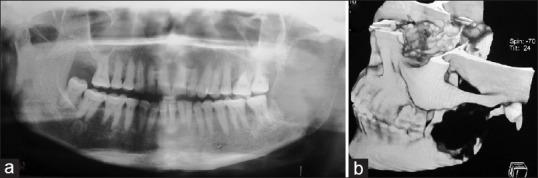

Clear cell odontogenic carcinoma of the mandible and temporomandibuar joint with cervical lymph nodal metastasis.

Clear cell odontogenic carcinoma (CCOC) is a rare aggressive tumor that has the ability to invade locally as well as cause regional and distant metastasis. The etiology of this neoplasm remains poorly understood and the diagnosis of CCOC is done by exclusion of other clear cell tumors. To date, approximately 75 cases of CCOC have been described in the English literature, all involving a single jaw. The majority of cases have been reported to arise from the mandible, the maxilla is less frequently involved, and no case had involvement of the temporomandibuar joint. Lymph node metastasis at initial presentation is reportedly rare (<10%). We describe possibly the first case of CCOC in a 50-year-old woman with involvement of the mandible and the temporomandibuar joint along with cervical lymph nodal metastasis. We share our experiences and challenges in the management of this unusual tumor.